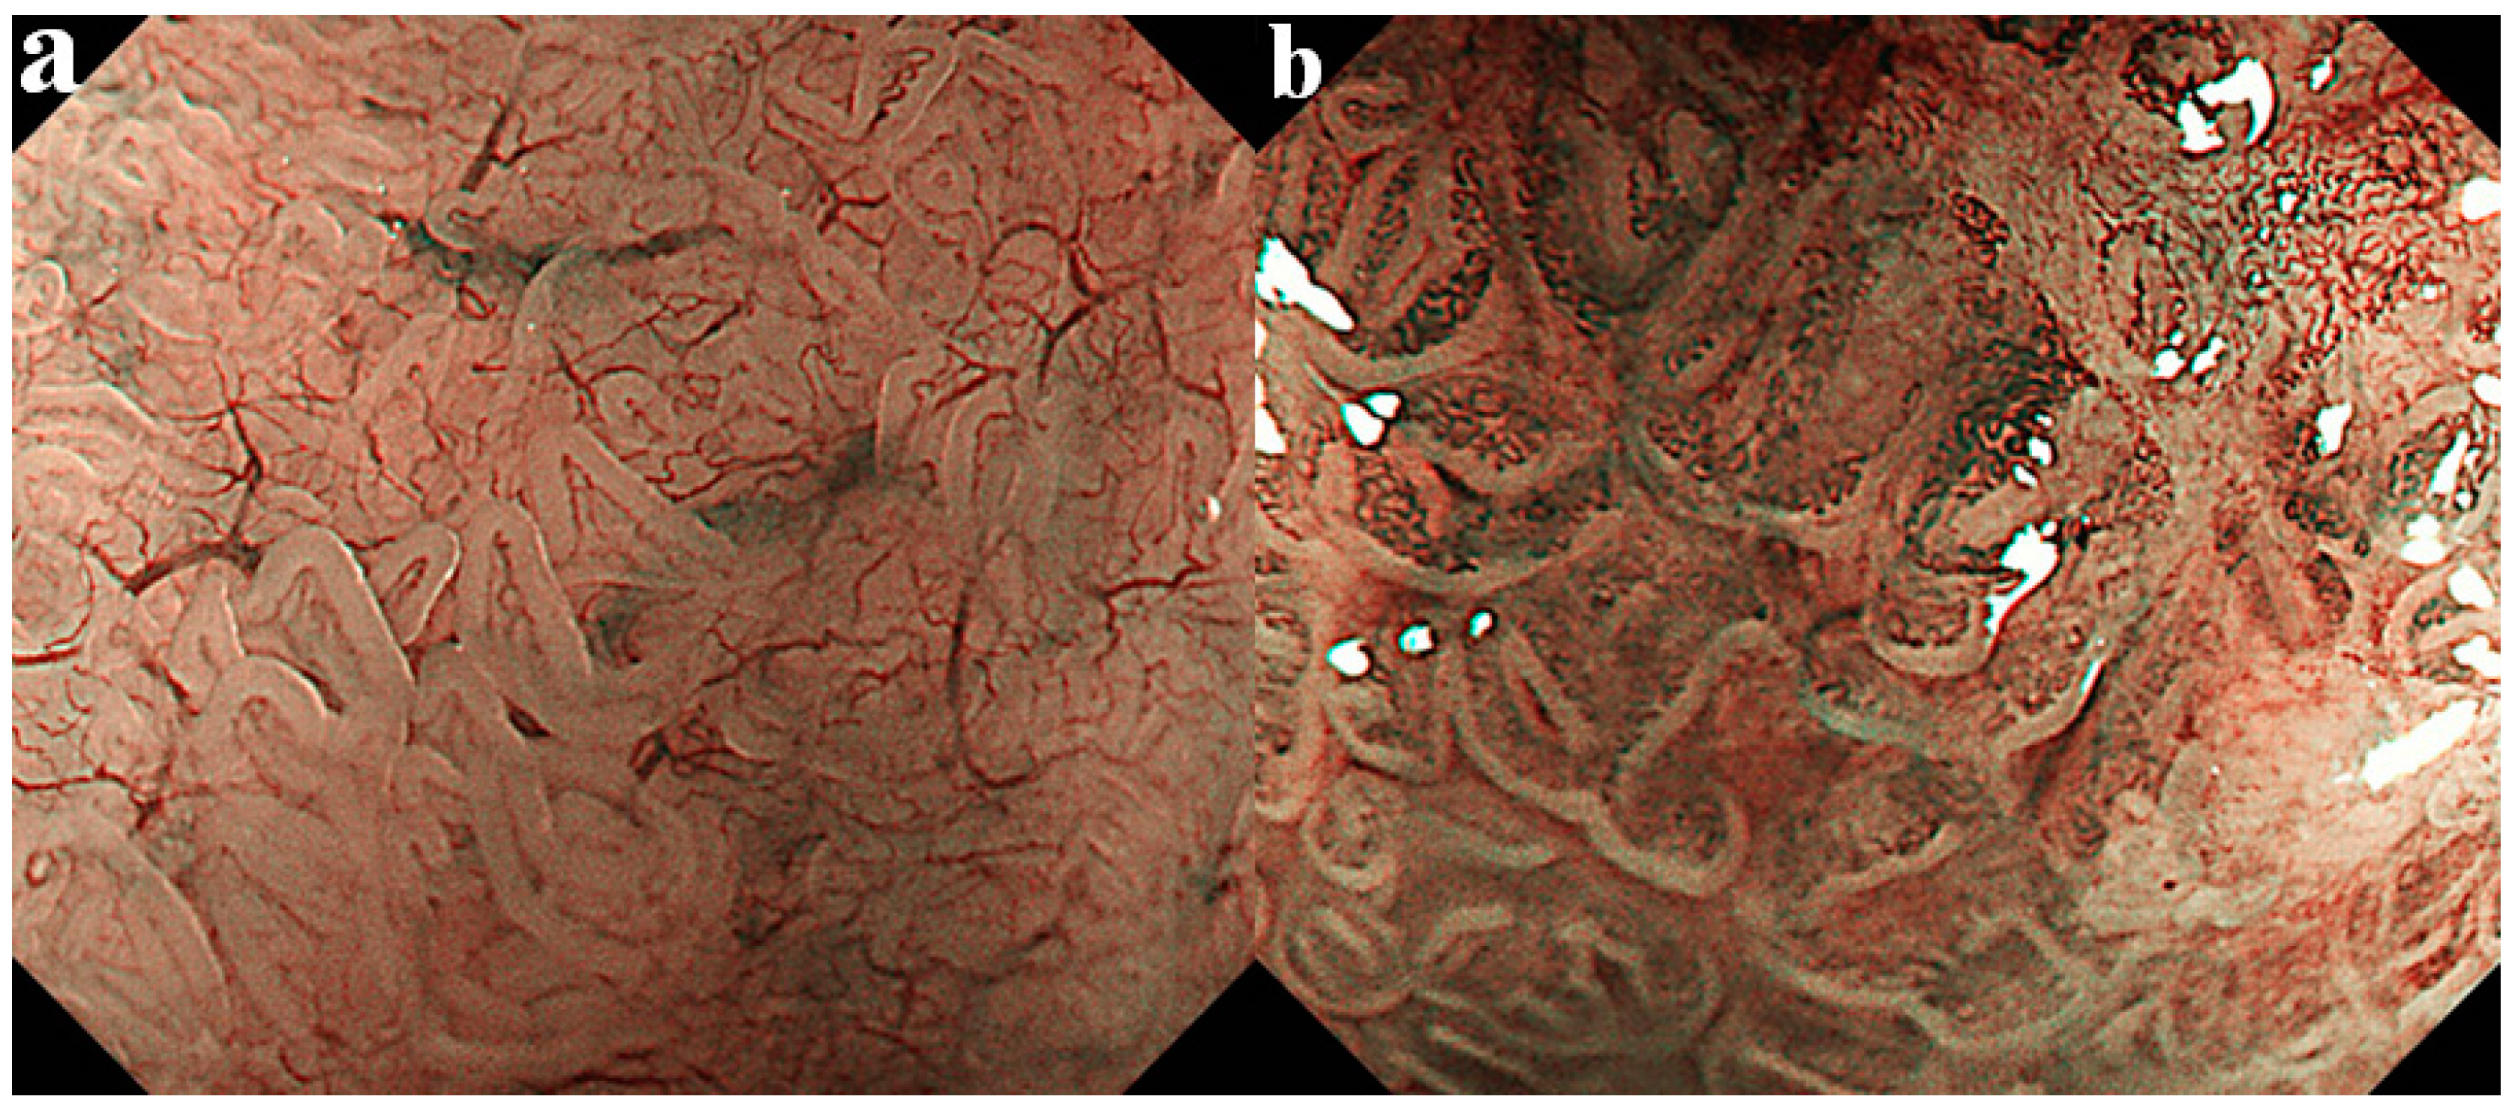

- Amano, Y.; Kushiyama, Y.; Ishihara, S.; Yuki, T.; Miyaoka, Y.; Yoshino, N.; Ishimura, N.; Fujishiro, H.; Adachi, K.; Maruyama, R.; et al. Crystal violet chromoendoscopy with mucosal pit pattern diagnosis is useful for surveillance of short-segment Barrett’s esophagus. Am. J. Gastroenterol. 2005, 100, 21–26. [Google Scholar] [CrossRef] [PubMed]

- Yuki, T.; Amano, Y.; Kushiyama, Y.; Takahashi, Y.; Ose, T.; Moriyama, I.; Fukuhara, H.; Ishimura, N.; Koshino, K.; Furuta, K.; et al. Evaluation of modified crystal violet chromoendoscopy procedure using new mucosal pit pattern classification for detection of Barrett’s dysplastic lesions. Dig. Liv. Dis. 2006, 38, 296–300. [Google Scholar] [CrossRef]